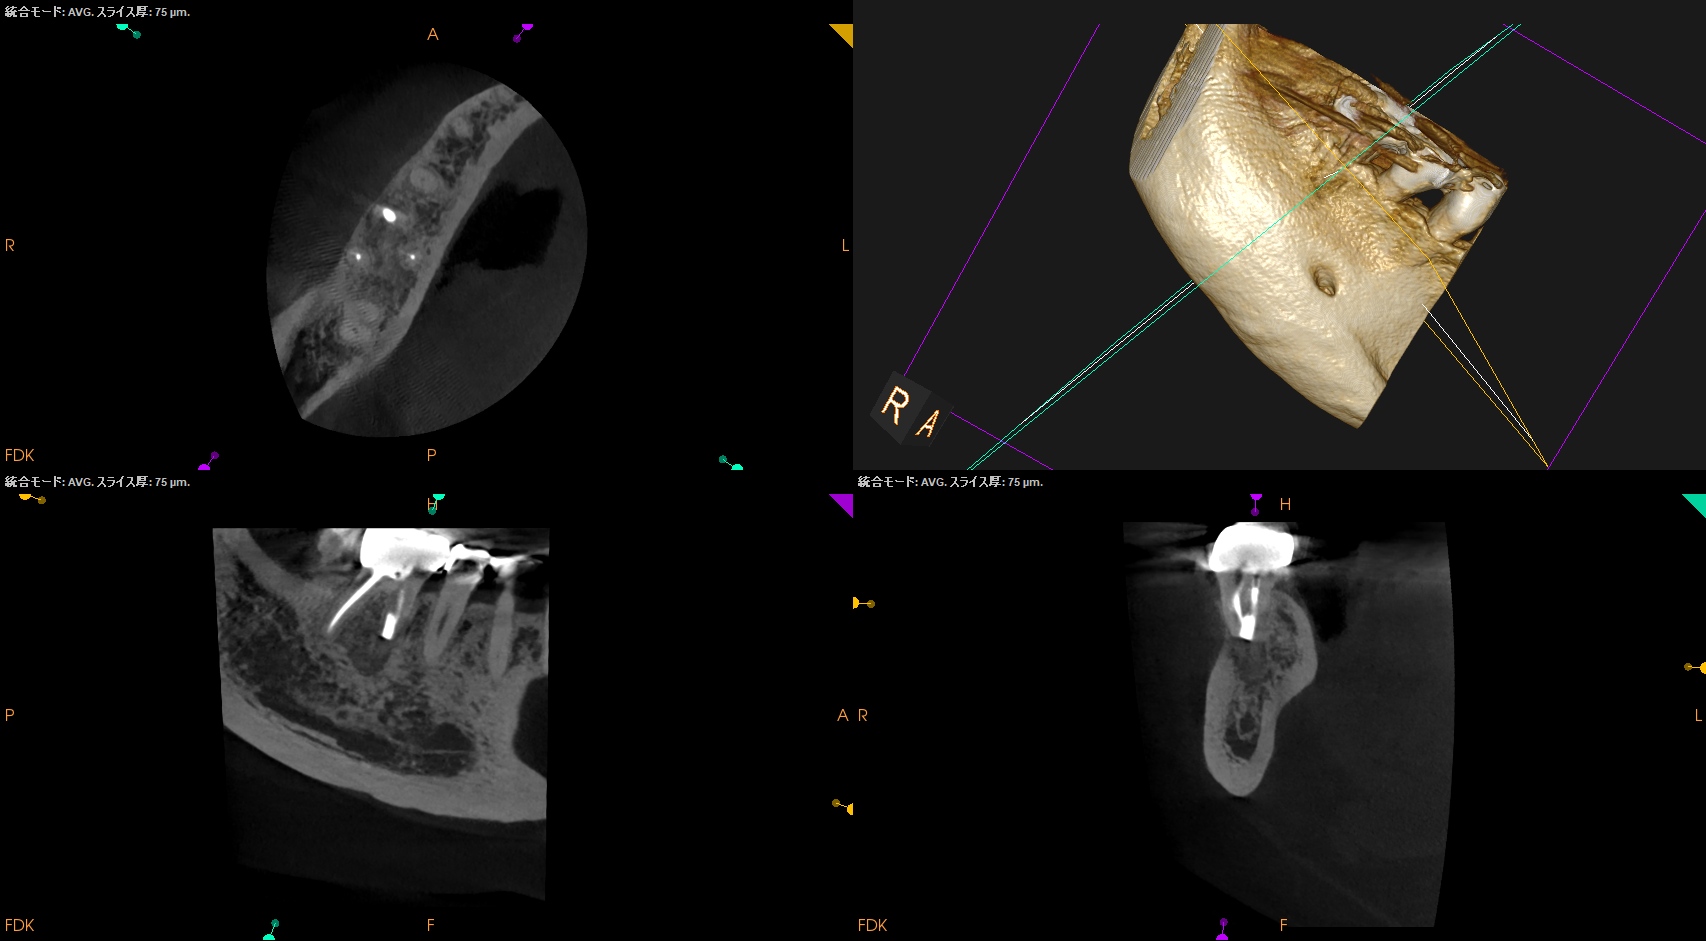

#30 M Apicoectomy 6M recall(2026.2.18)

大幅に問題が改善している。

初診時と比較した。

歯槽骨が劇的に再生している。

臨床症状もない。